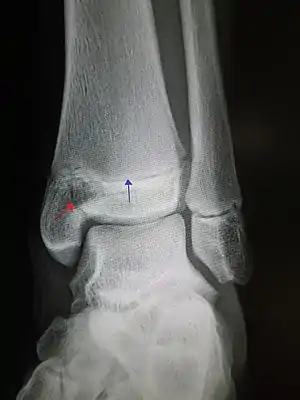

Pott's fracture[5]Percival Pottbimalleolar fracture of the ankleeversion of anklePott's fracture at Who Named It?